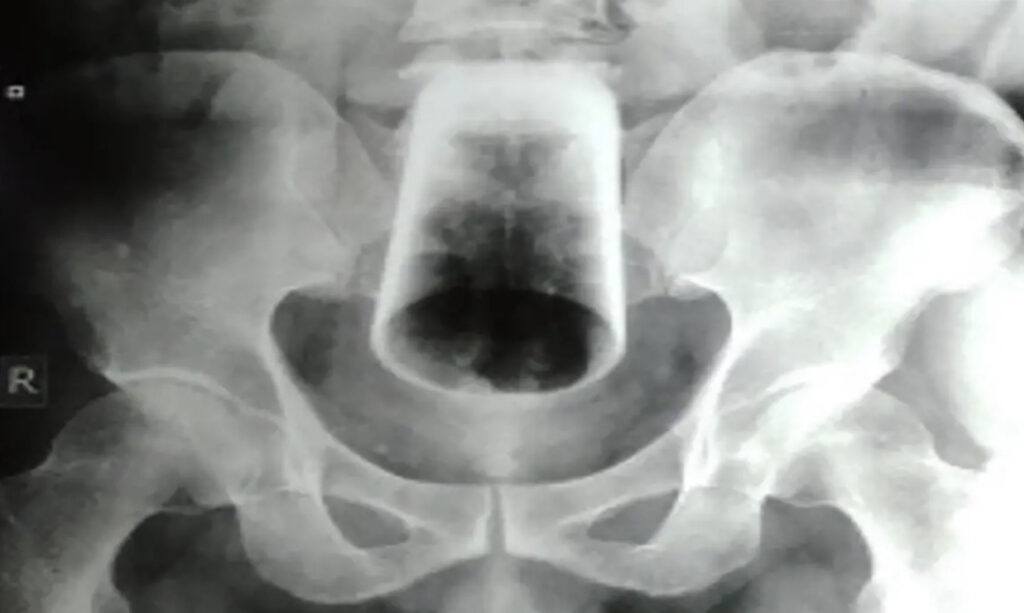

Dva dana nije imao stolicu, no imao je vjetrove i nije krvario. Ipak, trpio je strašne bolove. Doktorima je kazao da je sam pokušao izvaditi čašu, ali nije uspio. Nakon što su ga snimili rendgenom, doktori su pokušali izvući čašu, ali nisu uspjeli jer se okrenula, pa je morala van operativnim putem.